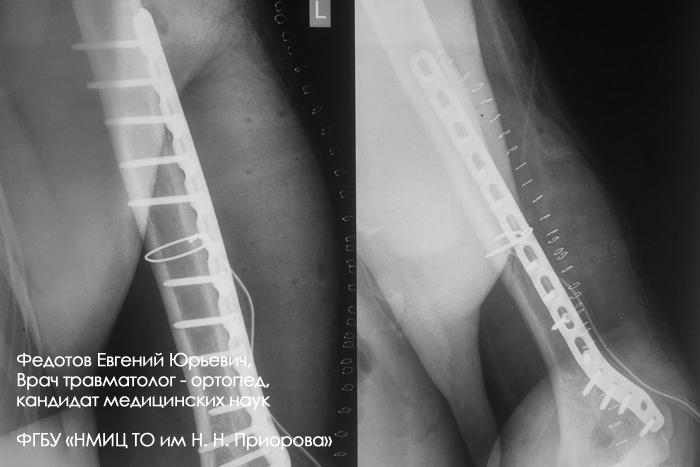

Пациент с оскольчатым переломом среднего отдела плечевой кости.

Выполнена операция: металлоостеосинтез плечевой кости стержнем с блокирующими винтами, введенным ретроградно.

Гипсовая повязка после операции не применялась, сразу после операции начата физкультура для суставов и мышц конечности.

Результат через 4 мес. после операции.

Видно, что мышцы, функция суставов полностью восстановились.

Пациентка с переломом среднего отдела плечевой кости.

Результат через 2 мес. после операции.

Функция конечности полностью восстановились.